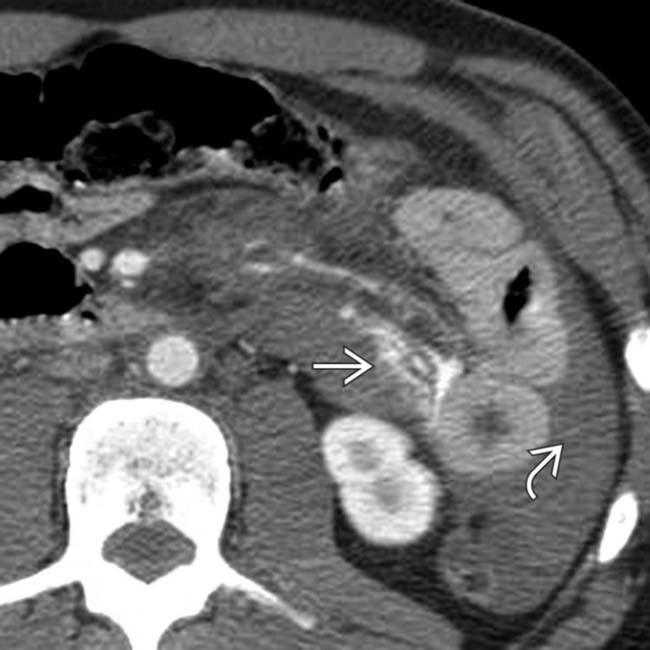

Here are a few signs of abdominal injuries after a car wreck: Thus eliminating the body's response for a necessary bowel movement. Common causes of stomach pain after a car accident include internal bleeding, organ damage, blood vessel damage, organ rupture, or internal aggravation.

Son is a fireman/emt and the tenderness in the stomach following an accident with one wearing a seat belt is one of their top priorities. The delayed reaction to the impact of a car accident can lead to stomach pain. Bowel obstruction small bowel obstruction is a blockage in the small intestine.